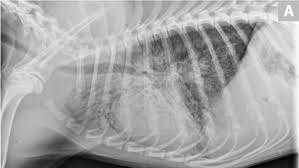

The vet will look for nasal discharge, coughing, take the temperature of the dog, and listen to the lungs using a stethoscope. Severe symptoms in combination with poor appetite could. A veterinarian will perform a full physical examination on a dog after an owner notes symptoms that are characteristic of pneumonia. But in some rare cases, it may be a lung cancer (primary or secondary). Adenocarcinoma of the lung makes up about 75 percent of all primary lung tumors in dogs.

Types Treatments Symptoms Of Lung Cancer In Dogs Plains Veterinary Oncology Northeast Veterinary Referral Hospital from d2zp5xs5cp8zlg.cloudfront.net Lung cancer is sometimes found this way. Symptoms of lung cancer are coughing (which may also produce phlegm or blood), exercise intolerance (lethargy), weight loss or loss of appetite, and other respiratory signs such as trouble breathing or shortness of breath. Antibiotics may be prescribed to treat pneumonia. A veterinarian will perform a full physical examination on a dog after an owner notes symptoms that are characteristic of pneumonia. Usually, this is a sign of your dog's body fighting the infection, but if your dog overheats, it could be dangerous or even fatal. Some severely affected dogs may have extreme exercise intolerance. Sometimes, people with pneumonia may have symptoms similar to lung cancer. However, primary lung cancers are being seen more frequently over the last 20 years.

Just like pneumonia in people, pneumonia in dogs is a serious health condition and. Usually there are no symptoms in the early stages of canine lung cancer. There are times when coughing may mean your dog has lung cancer. Most primary lung tumors are diagnosed at an average age of 10 to 12 years in dogs. A veterinarian will perform a full physical examination on a dog after an owner notes symptoms that are characteristic of pneumonia. These signs are not specific for bronchitis and can also be seen with many other diseases including heart failure, pneumonia, allergic lung disease and lung cancer. Adenocarcinoma of the lung in dogs. It is characterized by a moist, bubbling cough and fever. However, primary lung cancers are being seen more frequently over the last 20 years. Some of the pneumonia symptoms overlap with those of the cold, but the condition also has discerning symptoms of its own. Primary lung tumors average cost. It usually results in mild symptoms, mild or no pneumonia, and it resolves within 5 to 7 days. Sometimes, people with pneumonia may have symptoms similar to lung cancer.

Metastatic cancer to the lungs is much more common than primary lung cancer. Usually there are no symptoms in the early stages of canine lung cancer. Pneumonia can be mild and only require a week of treatment before you can. Lung cancer (adenocarcinoma) average cost. Pulmonary fibrosis in dogs is a deadly lung disease where the lungs become scarred, stiff, and thickened, resulting in breathing problems and low oxygen levels in the blood. None of these symptoms are definitive on their own, as the signs of lung cancer can be similar to the signs seen in dogs suffering from other health conditions, like heart failure, pneumonia, or a heartworm infection. Read on and learn more about the symptoms, causes, and treatment of pneumonia in dogs. Lung tumors have moderate to high potential for metastasis (spreading). Melanomas in dogs tend to affect the mouth and lips, and they can also be found on their nail beds, footpads and eyes. Lung cancer is sometimes found this way. When coughing may mean your dog has lung cancer. Canine distemper virus, adenovirus types 1 and 2, canine influenza virus, and. There are many possible causes.

Lung Cancer In Dogs Causes Signs Treatment Canna Pet from g77v3827gg2notadhhw9pew7-wpengine.netdna-ssl.com Primary lung tumors, also known as pulmonary tumors, are frequently malignant and require surgery to remove both the growth and a significant portion of the lung. Pneumonia in dogs can have different causes: It usually results in mild symptoms, mild or no pneumonia, and it resolves within 5 to 7 days. Melanomas in dogs tend to affect the mouth and lips, and they can also be found on their nail beds, footpads and eyes. Pneumonia is a common lung infection. Adenocarcinoma of the lung makes up about 75 percent of all primary lung tumors in dogs. Sometimes, people with pneumonia may have symptoms similar to lung cancer. If your dog's pneumonia progresses without responding to treatment, your vet may recommend more extensive diagnostics to get to the root of the problem.

The cause can be bacteria, a virus, or fungi. Symptoms of primary and metastatic lung cancer are similar, although dogs with metastatic disease don't cough as much, according to the merck veterinary manual. It is also possible that a cancer diagnosis can be delayed if the cancer is mistaken for pneumonia. Unlike some other types of cancer, there are some concerning symptoms that arise in the earlier stages of primary lung cancer for dogs that should immediately alert you that something is wrong. Most primary lung tumors are diagnosed at an average age of 10 to 12 years in dogs. When they do cough, they might bring up blood. Pneumonia in people with lung cancer. It is caused by a viral or bacterial infection in the respiratory tract. Primary lung tumors average cost. Lung cancer is sometimes found this way. Canine distemper virus, adenovirus types 1 and 2, canine influenza virus, and. Some of the symptoms may include: Some of the pneumonia symptoms overlap with those of the cold, but the condition also has discerning symptoms of its own.